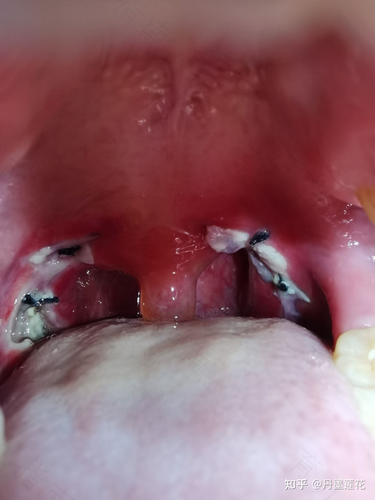

当发现扁桃体上有了白色的东西时候,说明这时候的扁桃体已经出现了化脓情况,这样的情况要进行消炎治疗,如果可能的话还需要通过输液的方式来帮助消炎,这样才能够让自己的扁桃体化脓问题可以得到及时解决。